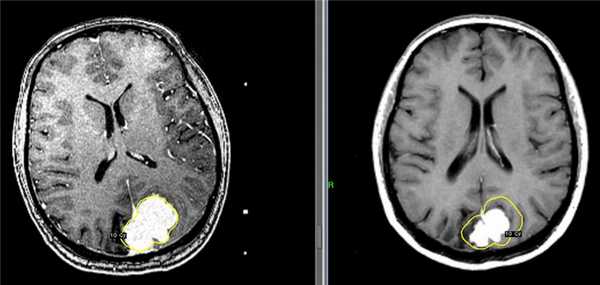

Слева - МРТ пациентки К., 47 лет. Обратилась в Клинику радиохирургии МИБС с диагнозом: рецидив после хирургического удаления парасагиттальной менингиомы верхней трети ВСС и фалькса. Размер опухоли 31 мм х 46 мм х 34 мм, объем 19 см3. Проведен сеанс стереотаксической радиохирургии. Доза по краю опухоли 10 Гр (показана желтым цветом).

Справа - контрольное МРТ пациентки К. через 6 месяцев после радиохирургического лечения на Гамма-ноже в Клинике радиохирургии МИБС. Отмечается выраженное уменьшение опухоли. Размер опухоли 19 мм х 31 мм х 24 мм, объем 7,2 см3. Уменьшение объема на 11,8 см3 (на 62%). Для наглядности желтым цветом приведена доза по краю опухоли на день лечения.